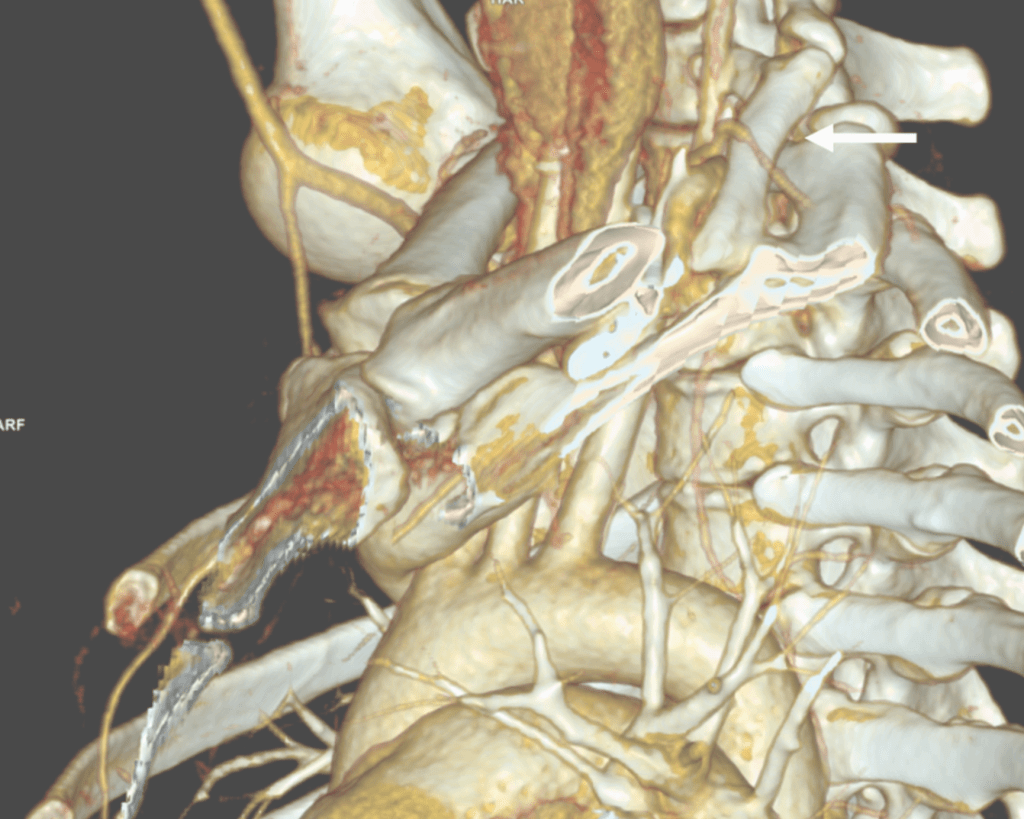

The patient is a younger woman who was referred from cardiology after workup of chest pain and left arm pain was negative for cardiac disease. She also had occasional right arm pain. The only finding of note during an extensive cardiac workup were cervical ribs found bilaterally on chest x-ray (below).

On examination, she was petite and had narrow shoulders. Stress maneuvers extinguished the arterial pulse in both extremities. EAST test was vaguely positive -weakness and numbness in the fingertips. Tapping on the cervical ribs which were prominent bumps in the supraclavicular fossae triggered shooting discomfort in both arms. I ordered a CT scan with contrast -this helps with operative planning as the 3D reconstructions allow you to view the operation before you perform it.

White arrow points to left cervical rib. The artery and plexus which is not seen are draped over it.